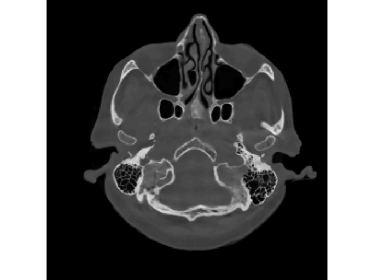

When the detectable range is smaller such that κ=0.4pmax𝜅0.4subscript𝑝\kappa=0.4p_{\max}, saturation becomes worse. Then the performance of FBP and SART, even with water cylinder extrapolation and the ISD scheme, dramatically drops. In practice, this heavy saturation rarely happens and is out of the scope of FBP-WCE. But even with this heavy saturation, the proposed M1bit-CSR-ISD can output a good result. The reconstructed images and enlargements of a region are illustrated in Fig.12 and Fig.13, respectively. In this case, both FBP-WCE and SART-ISD fail to restore the clear outer boundaries of the patient, while M1bit-CSR-ISD is still able to achieve this in a more accurate manner. We further report the saturation detection result in Fig.14, from which one can observe that most of the saturations have been properly detected.

Figure 12: Reconstruction results for the clinical data (κ=0.4pmax𝜅0.4subscript𝑝\kappa=0.4p_{\max}): (a) ground truth (yellow rectangle is enlarged in Fig.13); (b) FBP-WCE; (c) SART-ISD; (d) M1bit-CSR-ISD.